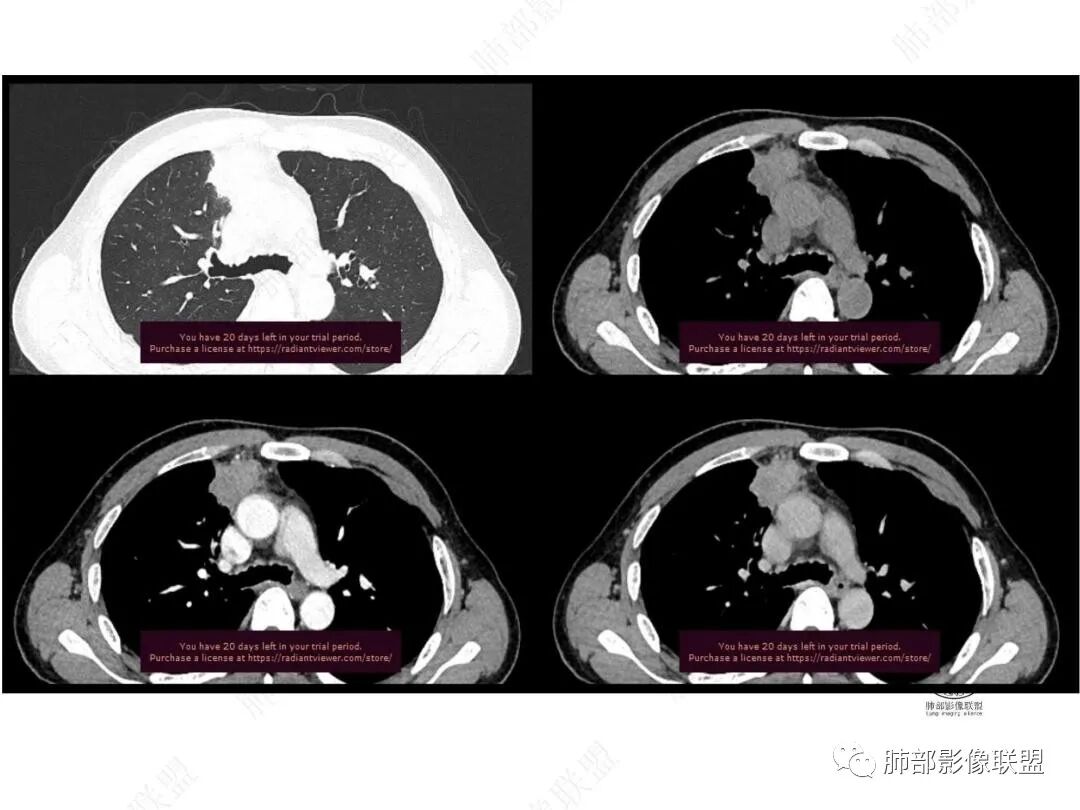

平扫图像

增强图像

CT值信息

中年男性,前纵膈旁团块,边缘平直,周围可见模糊的磨玻璃影,相邻支气管壁增厚,部分支气管进入病灶后阻塞,增强病灶渐进性强化,肝右叶见边缘不清的低密度影,增强渐进性强化。结合实验室检查,总体考虑炎性病变,自免性炎症?血管炎?

中年男性,右前纵隔旁不规则实变影,局部支气管进入后截断,病灶渐进性强化。肝脏右叶低密度灶,边界不清,呈明显渐进性强化。IMT?

男,49,低热3月。胸部CT:右肺上叶前段纵隔旁见团片影,部分边缘毛糙,部分平直、内收,邻近卫星灶、晕征,重建L征?支气管管壁增厚、进入后堵塞;纵隔可见肿大淋巴结;病灶密度较均匀,中度强化。肝脏片状低密度影,边缘模糊。考虑炎性病变,PC?TB?鉴别腺癌。

中年男性,反复低热3月伴近期乏力及右上腹隐痛,白细胞,中性粒及淀粉样蛋白A增高,PCT不高,IGA、IGg增高,类风湿因子增高,未提供IGg4水平,影像改变,左侧肋骨陈旧性骨折(2020年已存在)右上叶前段胸骨旁的胸膜下新发病灶,支气管进入后一段才堵塞,肺动脉进入,走行自然,未见破坏,明显均匀强化,气管及支气管壁有增厚,钙化,纵隔内淋巴结增大,均匀强化,无坏死,纵隔内脂肪混浊,局部强化,肝内低密度灶,延迟强化(肺内病灶,淋巴结、混浊脂肪,肝内病灶强化均一致,且均为延迟强化)。初步考虑:免疫相关性炎症,IGg4相关炎症可能大,依据:IGA、IGg增高(未提供IGg4,可能是故意隐藏了),类风湿因子增高,炎性指标增高,但PCT不高,细菌感染可能就变小,加上病变同时累及肺、纵隔淋巴结,纵隔内脂肪、肝。

与胸膜关系:糊墙

这里是软组织密度,纵隔内突入

我觉得这里可以怀疑是栽桩。

2.右肺上叶纵隔旁新发实性密度病灶,密度均匀,轻度强化,未见空洞、液化坏死及钙化,血管穿行自如,支气管进入后狭窄截止。灶周磨玻璃影边界不清,病灶未见明显分叶毛刺,平直、轻度收缩、周围偶见结节影,但未见树芽征。注意纵隔胸膜侵入或突入比较明确。纵隔淋巴结轻度增大。

3.右肺容易想到的病变有慢性炎症、IGg4相关、新生物(炎性肌纤维母细胞瘤、腺癌等)。但病灶侵入纵隔胸膜应当更符合恶性肿瘤。病程进展及强化等影像特点不支持继发性肺结核。